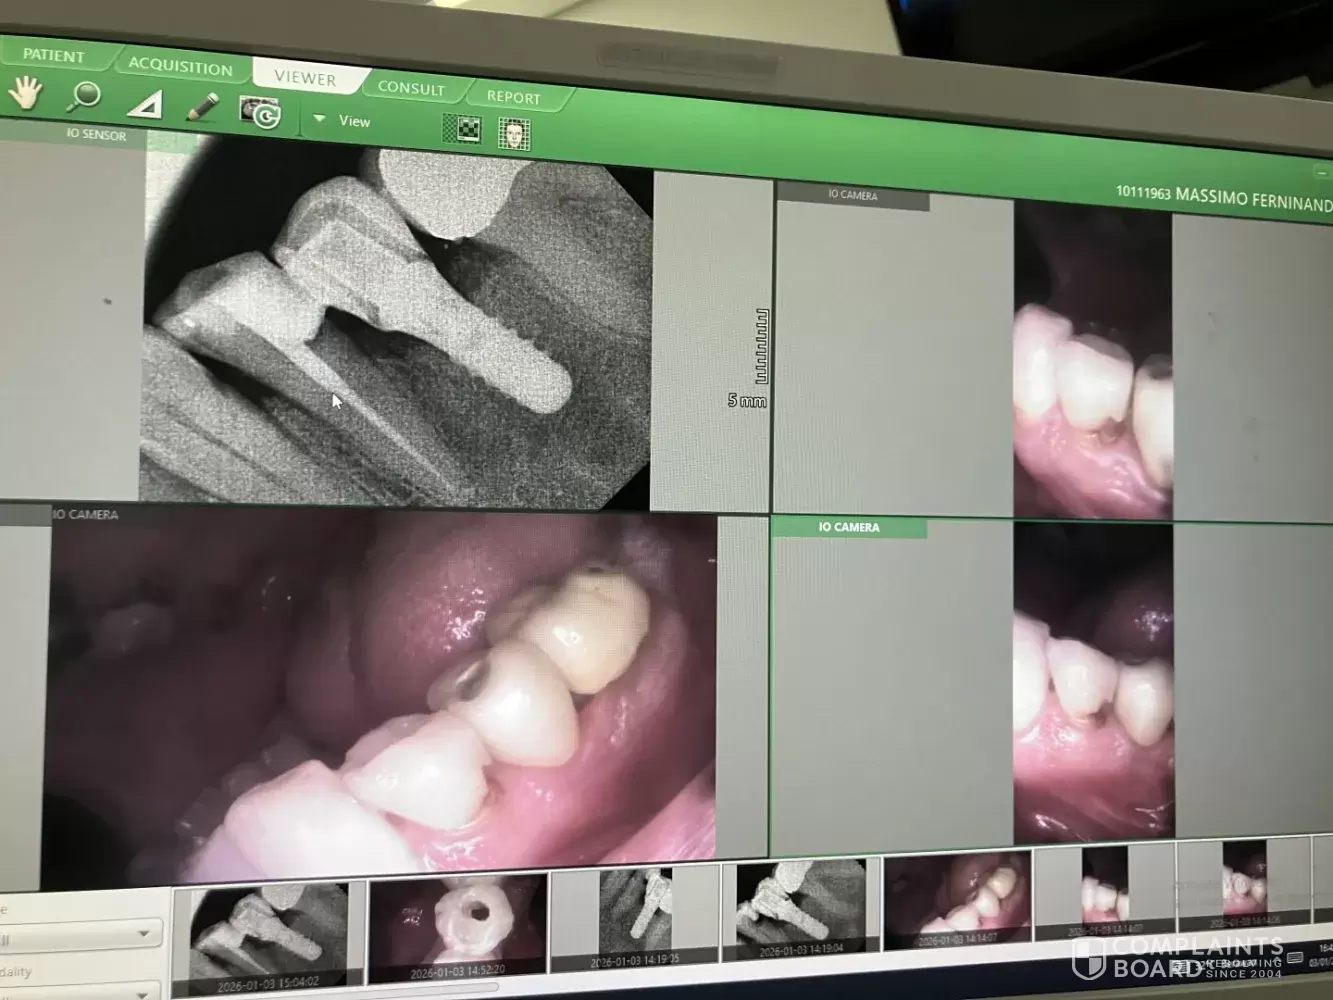

Totally wrong diagnosis! Luckily I contacted my dentist in Italy. I was feeling pain in the lower left part and he Q&M dentist found the cause in the top left part suggesting extraction or root canal. He made panoramic xray and checked all my tooth one by one and didn’t see an obvious cavity in the bottom left. Please check the attached photo! My Italian dentist suggested me to go to a dentist in Jkt. I went there and he found the obvious reason of my problem and he fixed it (root canal in the bottom left tooth: approx. Rp. 6.000.000). I hope the Q&M managers will contact me and open an investigation.